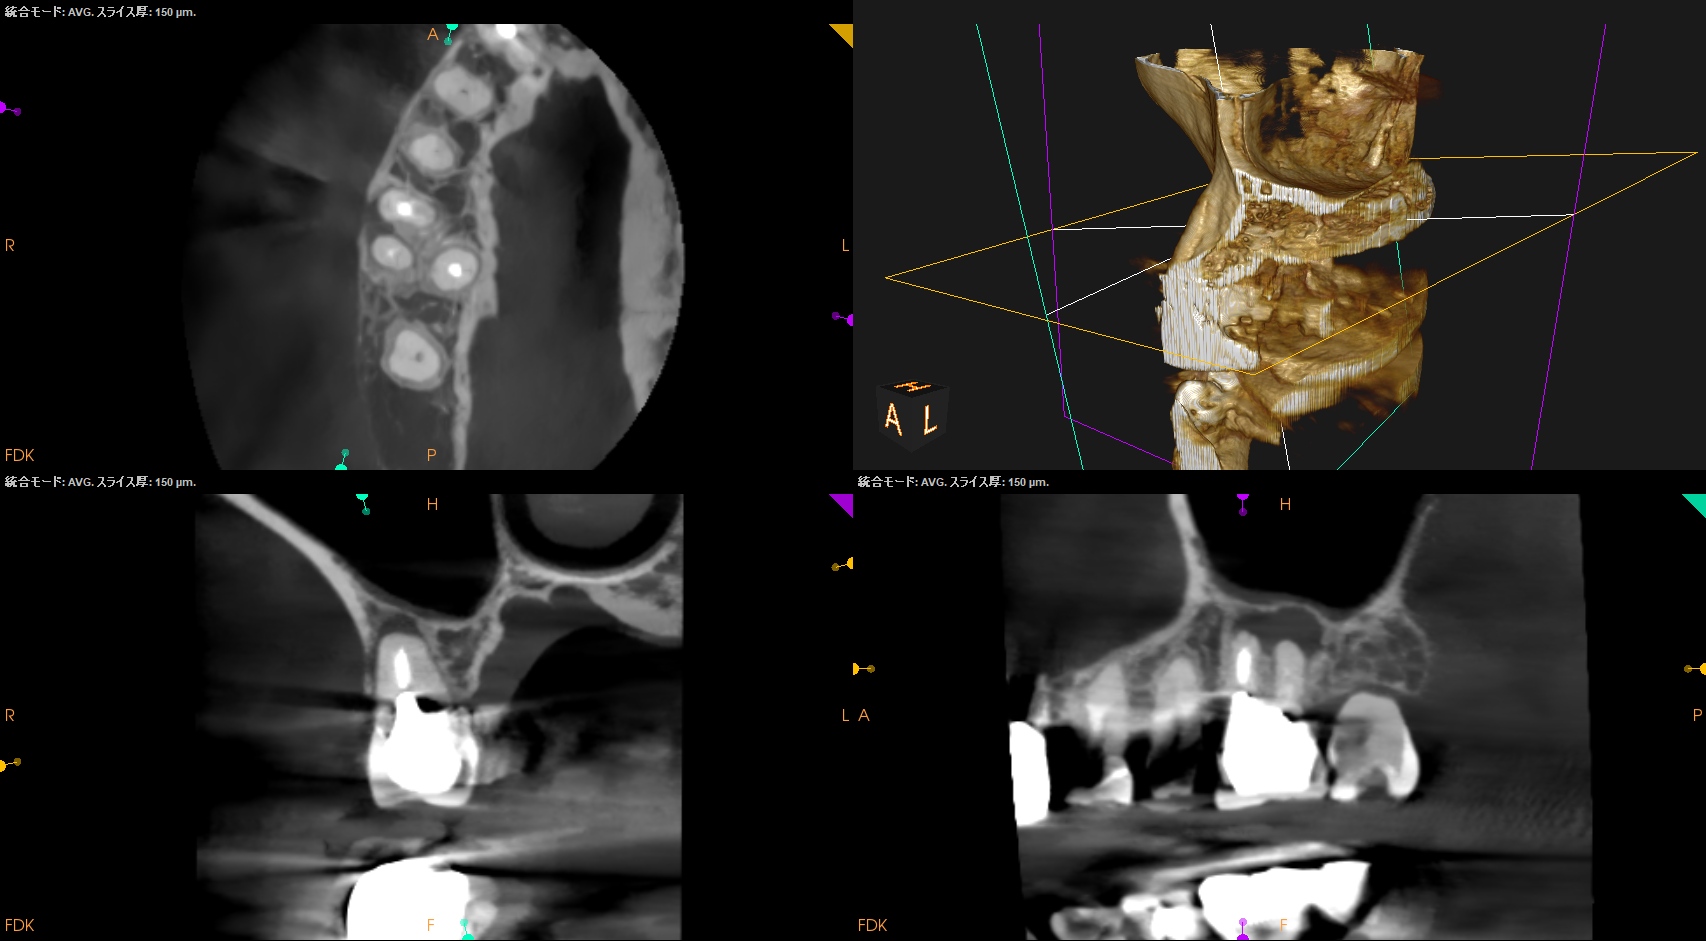

CBCT(2024.7.1)

#3

MB

DB

P

MB,DB,Pと3根全てに病変がある。

しかも形成が不完全だ。

再根管治療が濃厚である。

#14

MB,DBには病変がないが、Pに存在する。

これは頭が痛い。

パラタルフラップも困難なケースだからだ。

#16